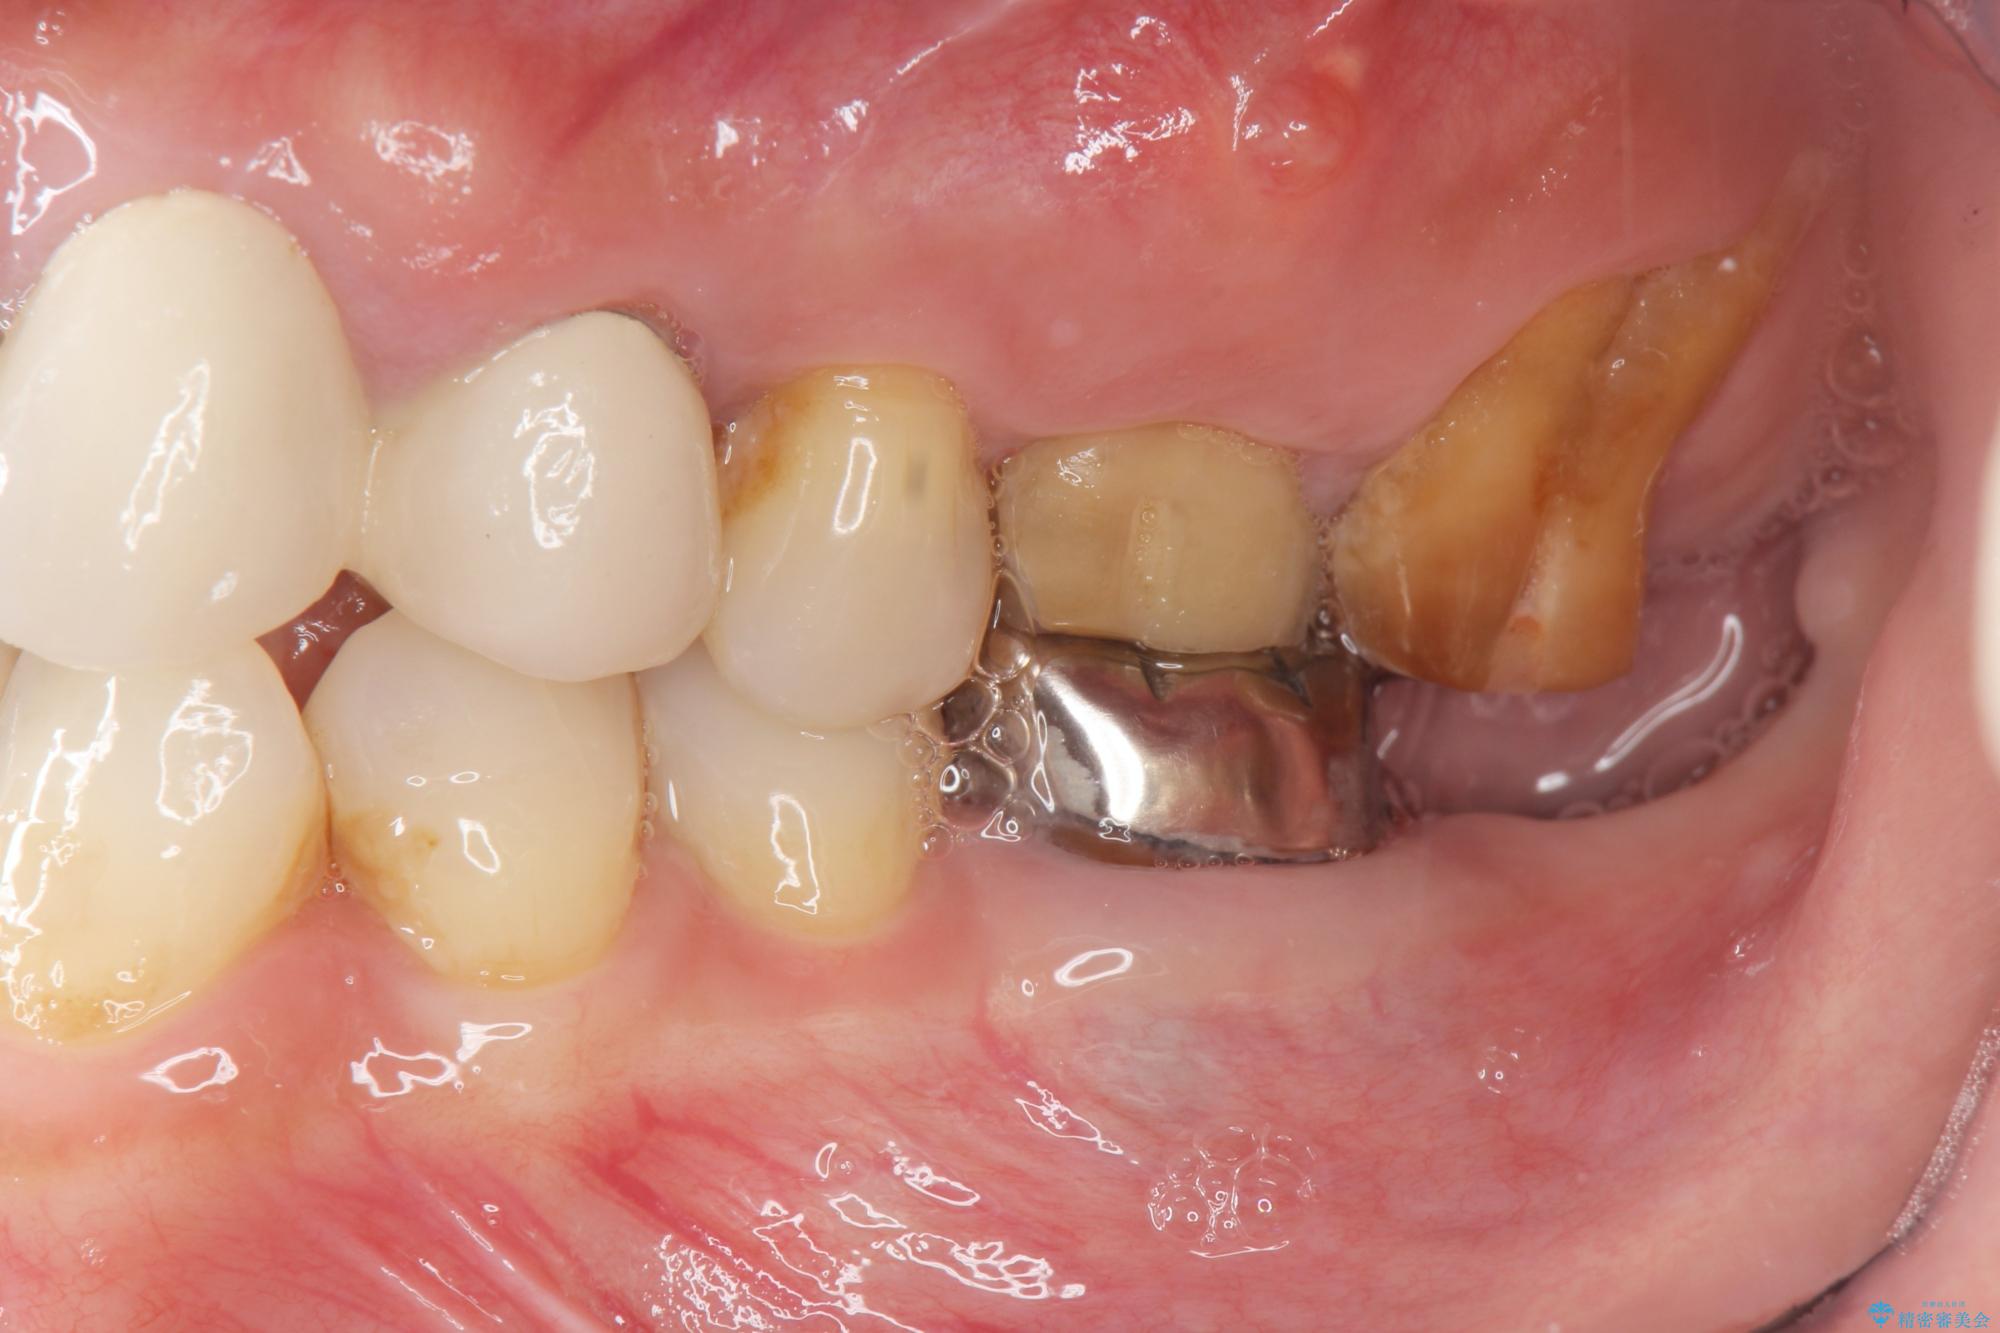

他院での治療の途中で通院をやめてしまい、当院で治療の続きを希望された患者様です。

クラウンが装着されておらず、つぎはぎだらけの処置歯を、精度の高いセラミッククラウンを用いて歯ブラシのしやすい環境整備を行っていきます。